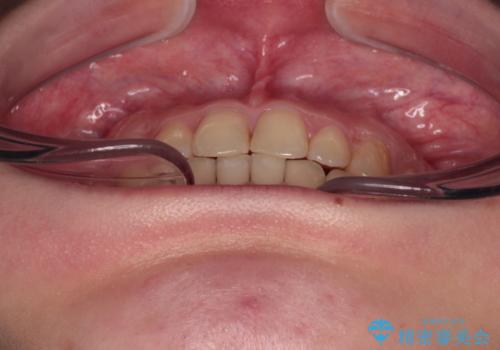

治療途中の奥歯と矯正治療の後戻り インビザライン・ライトによる矯正治療

- 20代女性

- インビザライン・ライト

- 根管治療を行ったままの奥歯と、矯正治療の後戻りを気にして来院された患者様です。

根管治療された歯に症状はなく、オールセラミッククラウンにて補綴治療を行うこととしました。

矯正治療の後戻りは軽微であったため、インビザラインの簡易パッケージであるインビザライン・ライトを用いて歯列を整えることとしました。

クラウンはよりよい咬み合わせで装着したいため、インビザラインを1セット使用して概ね歯列を整えた時点で補綴治療を行い、その後仕上げの矯正治療を行いました。